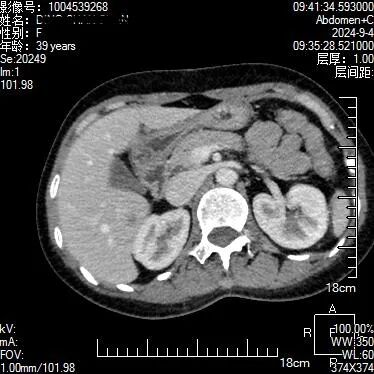

上腹部隐痛不适半个月,在当地医院就诊未发现明显异常,患者到贵州航天医院就诊,被检出肝脏肿瘤性病变,得到了及时诊治。 近日,一位39岁的女性患者在贵州航天医院就诊,通过该院最新引进的贵州首台飞利浦皓克双层探测器光谱CT,进行高精度扫描,该院医师利用光谱CT多参数能谱数据分析中的单能40KeV、碘密度图及有效原子序数功能,对患者进行了细致分析,医师在患者肝脏S6段发现一隐匿性肿瘤性病变,患者得以早期发现及时治疗。 采用光谱有效原子序数图 贵州航天医院医学影像科主任余雷向记者介绍,这个病例凸显了飞利浦皓克光谱CT对隐匿性肿瘤诊断的独特优势,其多参数光谱功能为医师提供了精确和更多的诊断依据,从而确保了患者病变的早期发现、得到及时准确的治疗。 余雷介绍,贵州航天医院为贵州省首家引进飞利浦皓克光谱CT,256排双层探测器的医院。皓克光谱CT扫描速度快、辐射剂量小,实时扫描既能产生光谱曲线、有效原子序列图、碘密度测量、尿酸及结石成分分析等16种不同参数的能谱数据图像,同时,在心血管、肿瘤、神经等系统的疾病准确诊断方面有其独特的价值,能够发现隐匿性肿瘤病灶,利用光谱曲线、碘定量测量等,可以准确分析肿瘤的良恶性,多发病灶的同源性;还能显示心肌缺血病灶,对血管斑块进行定量定性分析。 “目前,该设备已在我院放射科安装完成并投入使用。与传统CT相比,皓克光谱CT不仅提升了疾病鉴别诊断的准确性,还能指导临床个性化、精准化的治疗方案。”余雷介绍。 更多内容请关注遵义晚报视频号 ▼▼▼ 遵义晚报 4 审核:张小东 徐飞 责编 :胡笳